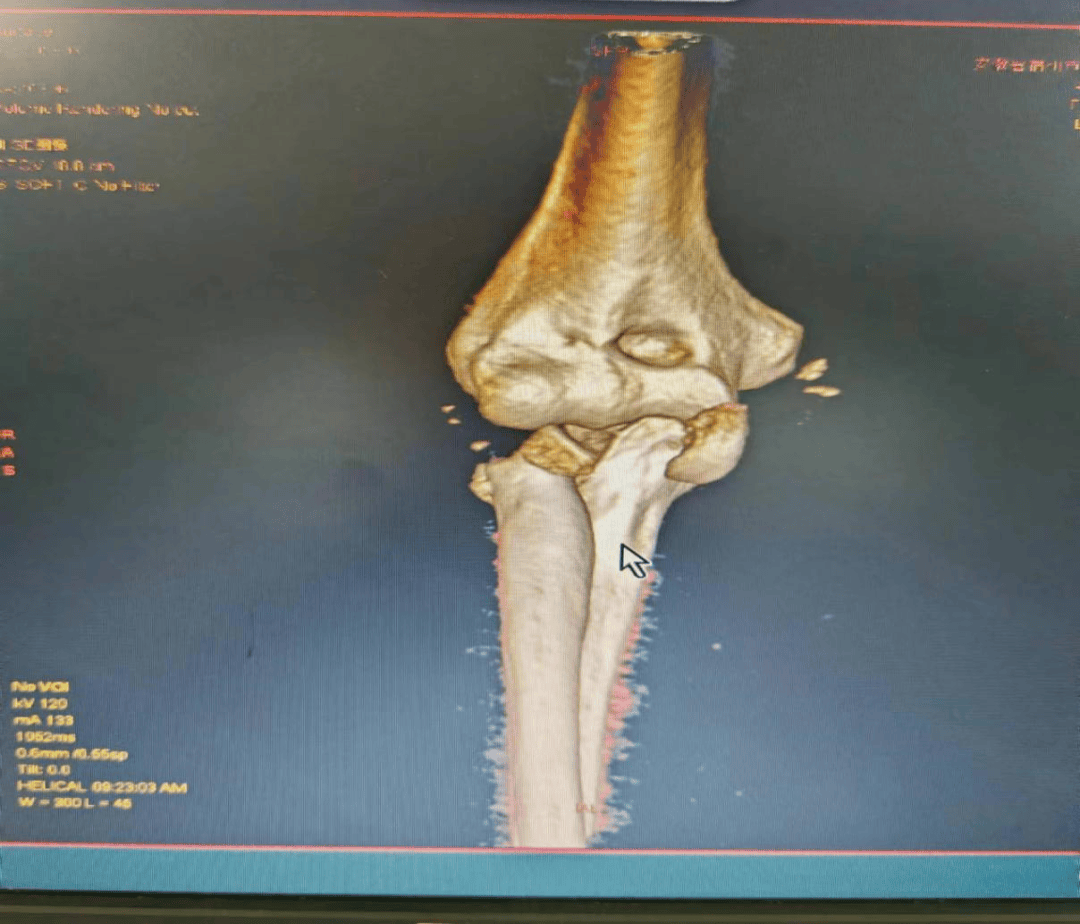

安徽省第二人民医院灵璧医院喻德富副院长、骨科博士、主任医师指导手术。术中探查发现胡女士桡骨头粉碎性骨折,骨碎片游离,尺侧副韧带、环状韧带断裂。骨科手术团队密切协作,按照规范手术治疗方案,小心取出碎骨块,放入假体稳定复位,锚钉重建尺侧受损韧带。术后石膏固定,消肿,预防感染,指导康复锻炼等治疗。

图为术后复查

王医师表示,桡骨头置换术的成功施行,体现了我院骨科针对复杂肘关节损伤的治疗能力和水平迈上了新的台阶。在今后的临床工作中,骨科将继续大力发展新技术,开展新项目,寻求新突破,不断提升技术水平,为全县患者提供更好地诊疗服务。